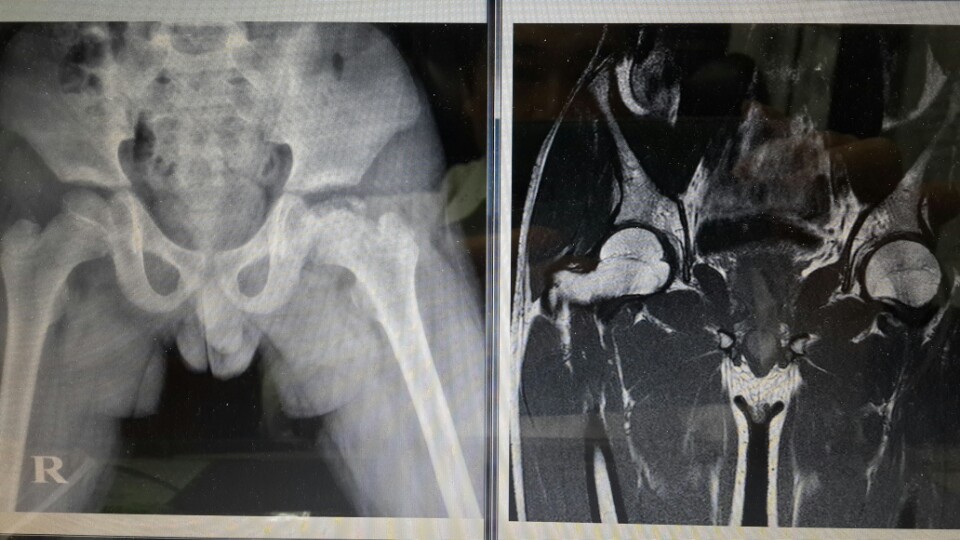

ÀÌ »çÁøÀº LCP (2001³â»ý ) ·Î ¹é»ïÇÑÀÇ¿ø¿¡¼ ÇѾà Ä¡·áÈÄ¿¡

ÂïÀº »çÁø ÀÔ´Ï´Ù.

ÁÂÃø »çÁøÀº 2011³â 9¿ù¿¡ ÂïÀº X-RAY »çÁøÀ̰í

¿ìÃø »çÁøÀº 2012³â 8¿ù¿¡ ÂïÀº MRI »çÁøÀÔ´Ï´Ù.

ÁÂÃøÀÇ »çÁøµµ °ñ±«»ç Ä¡·áÁß¿¡ ÂïÀº »çÁøÀ¸·Î óÀ½¿¡´Â À§·Î ½ñ¾ÆÀÖ´Â

Ÿ¿øÇüÀÇ °ñµÎ ºÎºÐ¾øÀÌ ¿ÏÀüÈ÷ ¼ºÀåÆÇ °¡±îÀÌ ¹«³ÊÁø »óÅ¿¡¼ ÇѾàÄ¡·áÁß¿¡

ÂïÀº °ÍÀÔ´Ï´Ù. ÀÌ¹Ì ¾àÈ¿°¡ ¹ßÈÖµÇ¾î ´ëÅð°ñµÎ »ó´ÜÀÌ ºÀ±ßÇÏ°Ô »ì¾Æ³ª´Â

¸ð½ÀÀ» º¼ ¼ö ÀÖ°í

¿ìÃøÀÇ »çÁøÀº 2012³â 8¿ù »çÁøÀ¸·Î¼, 2011³â 9¿ùÀÇ Å¸¿øÇüÀÌ´ø ´ëÅð°ñµÎ ¸ð¾çÀÌ,

µ¿±×¶õ °ñÇÁ°ø ¸ð¾çÀ» ¿ÏÀüÈ÷ ȸº¹ÇÏ´Â »óÅÂÀÇ °ñ±«»ç¸¦ º¼ ¼ö ÀÖ½À´Ï´Ù.